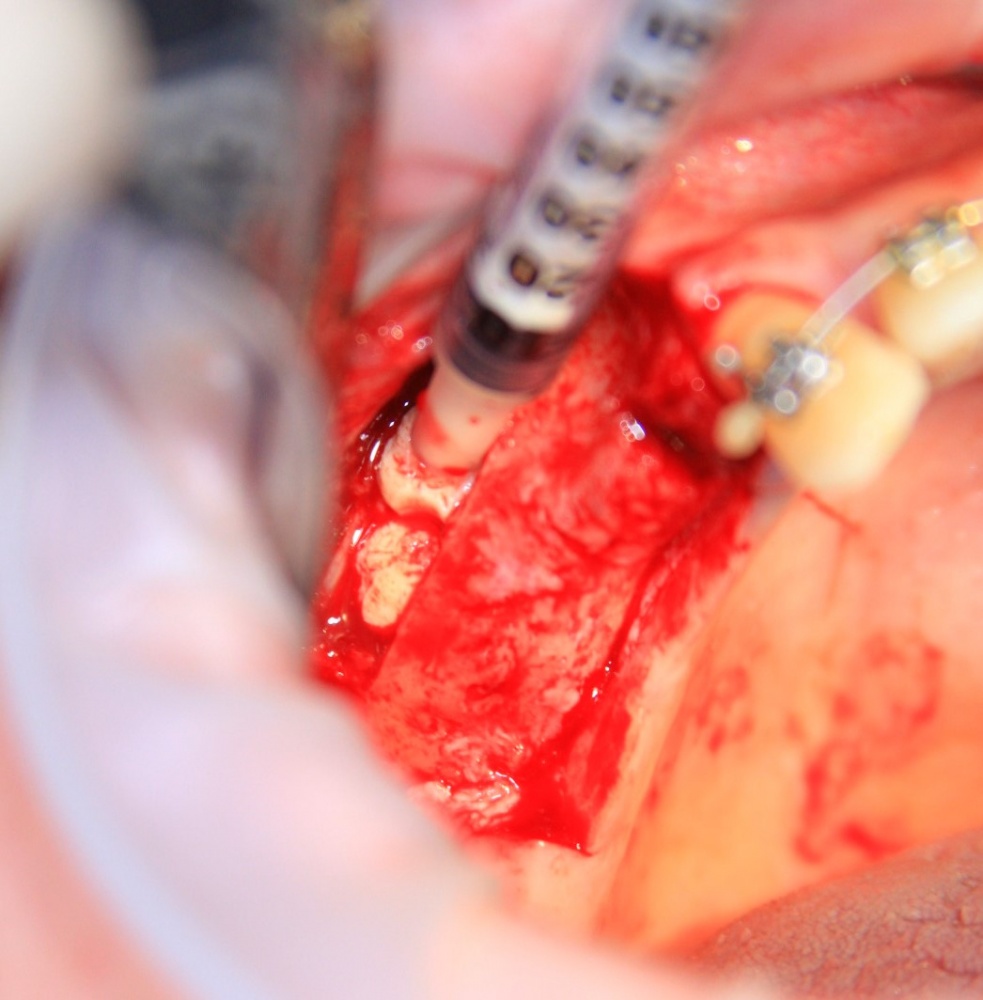

Я зафиксировал костный блок практически без адаптации на несколько винтов. Обрати внимание, что винты находятся в зоне, где не планируется установка имплантатов. Фиксация должна быть надежной, поскольку мне еще предстояла подготовка лунок для имплантатов. Трех винтов для этого вполне достаточно.

Дальнейшая адаптация костного блока свелась к сглаживанию острых краев. После чего я приступил к подготовке лунок и установке имплантатов.

Установка имплантатов.

Напомню, что для этой работы я выбрал субкрестальные имплантаты Ankylos C/X. Они прекрасно сочетаются с любым методом остеопластики.

Я не планирую установку супраструктур или коронок, поэтому на уровень первичной стабильности можно положить болт. Даже наоборот — чем меньше крутящий момент при установке, тем лучше. Для имплантатов Ankylos и подобных им, это особенно важно. В общем, момент силы при установке — не более 10-15 Нсм.

Ремарка: имплантаты с предустановленными имплантодержателями хороши тем, что с ними легко контролировать позиционирование имплантатов. В случае с Ankylos С/Х - еще и крутящий момент. Имплантодержатель должен отсоединяться от имплантата с легким щелчком. Если его клинит, и тебе приходится прикладывать для этого усилия, то ты, однозначно, превысил момент силы во время установки имплантата. Следовательно, жди проблем.

Глянем на то, что получилось:

Осталось адаптировать костный блок (убрать острые края), проверить его фиксацию и, при необходимости, добавить винты. Десятисекундное дело.